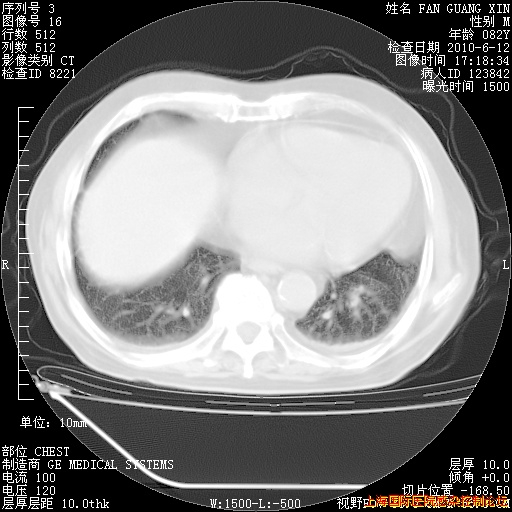

6月12日纵膈窗